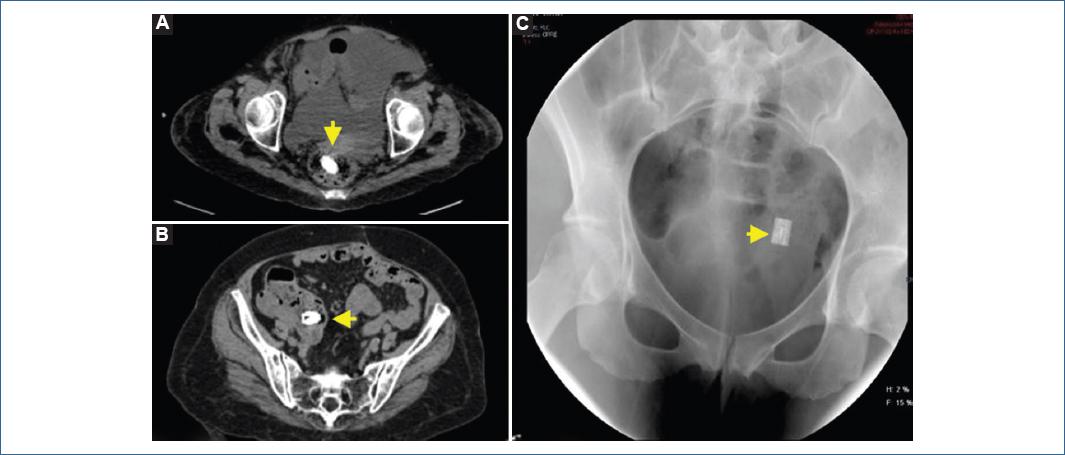

Cuatro pacientes expulsaron la cápsula de manera natural, mientras que dos presentaron retención de la misma. En los pacientes que presentaron excreción natural, solo uno la expulsó en las primeras 30 horas, por lo cual no requirió estudio de imagen. Tres pacientes la expulsaron después de 30 horas, por lo que en dos se realizó radiografía de abdomen y se complementó con tomografía de abdomen observando cápsula en recto y ciego respectivamente, mientras que en otro paciente se documentó la cápsula en recto por radiografía de abdomen (Imagen 1A, 1B y 1C respectivamente). De éstos, uno expulsó la cápsula después de 72 horas, la cual se encontró íntegra. Dos pacientes presentaron retención de la cápsula en íleon, en un pacientes fue retención asintomática documentada por tomografía y otro paciente desarrollo oclusión intestinal que resolvió espontáneamente (Imagen 2A y 2B, respectivamente).

Imagen 1 Localización de la cápsula por medio de estudios de imagen. A: Tomografía computarizada de abdomen con cápsula localizada en recto. B: Tomografía computarizada de abdomen con cápsula localizada en ciego. C: Radiografía de abdomen con cápsula localizada en recto.